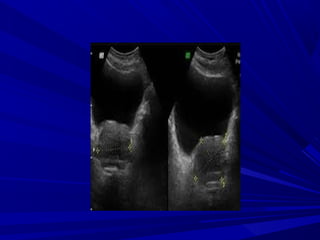

EVALUACIÓN ECOGRÁFICA

La evaluación de las glándulas adrenales

consiste en describir:

La posición,

La forma,

La ecogenicidad,

La arquitectura y

El tamaño de cada glándula adrenal.